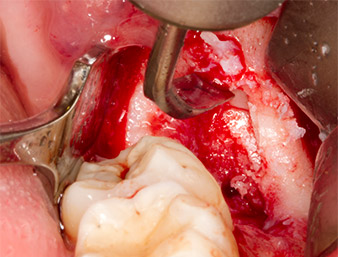

Tras una anestesia local y por conducción, el campo quirúrgico se abrió mediante los tejidos blandos para tener un acceso bucal-retromolar y se dejó expuesto (figura 3).

corte surcular

Imagen 3: El corte surcular comienza en el centro del diente 36, con alargamiento distal en la rama ascendente.

El tejido situado por encima del resto radicular no se había osificado por completo y constaba en su mayor parte de un tejido granulado con alteraciones inflamatorias (figura 4).

tejido granulado

Imagen 4: Dos ganchos de Langenbeck y un raspador según Prichard exponen el campo quirúrgico. Se distingue un tejido granulado de la primera osteotomía que no ha cicatrizado en su totalidad.